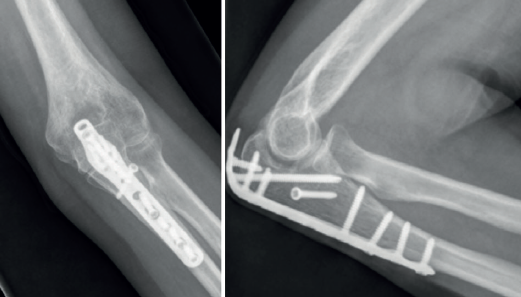

Las placas colocadas en la superficie posterior del cúbito son el sistema de fijación recomendado, proporcionando una fijación más resistente que los cerclajes con agujas de Kirschner y además permiten la fijación adicional de los fragmentos óseos y de la coronoides con tornillos o placas ortogonales en las superficies medial o lateral en los casos con gran conminución metafisaria(1,2,17). Las placas especialmente diseñadas de olécranon (Figuras 5 y 6) o las placas de compresión dinámica de contacto limitado (LC-DCP) de 3,5 mm conformadas para adaptarse a la morfología del cúbito son preferibles a las placas semitubulares, al aportar una fijación más estable(2,18,19).

Cuando la fractura del olécranon incluye una fractura de la coronoides, la reducción y la fijación de esta es condición imperativa para conseguir la estabilidad humerocubital (Figuras 7, 8 y 9). La reducción puede llevarse a cabo a través de la fractura del olécranon o por medio de un abordaje medial, separando o a través de la musculatura flexora/pronadora, teniendo identificados y protegidos el nervio cubital y el fascículo anterior del ligamento colateral medial. En los casos en los que es necesario realizar la sustitución de la cabeza del radio por una prótesis, también es posible el acceso lateral a la fractura de la coronoides. En general, el fragmento permite la fijación con tornillos desde posterior a anterior, a través de la placa posterior o independientes de esta, o en ocasiones desde anterior a posterior. La utilización de placas de 2,7 mm o específicas de coronoides, y técnicas de suturas no reabsorbibles atadas sobre el cúbito proximal o sobre la placa de fijación del cúbito son otras opciones(13,17). Para los grandes defectos óseos o fracturas irreconstruibles de la coronoides, se han descrito injertos óseos de la cresta ilíaca e injertos osteocondrales de la cabeza del radio con resultados impredecibles debido a la osificación heterotópica y a la reabsorción ósea del injerto(20,21).